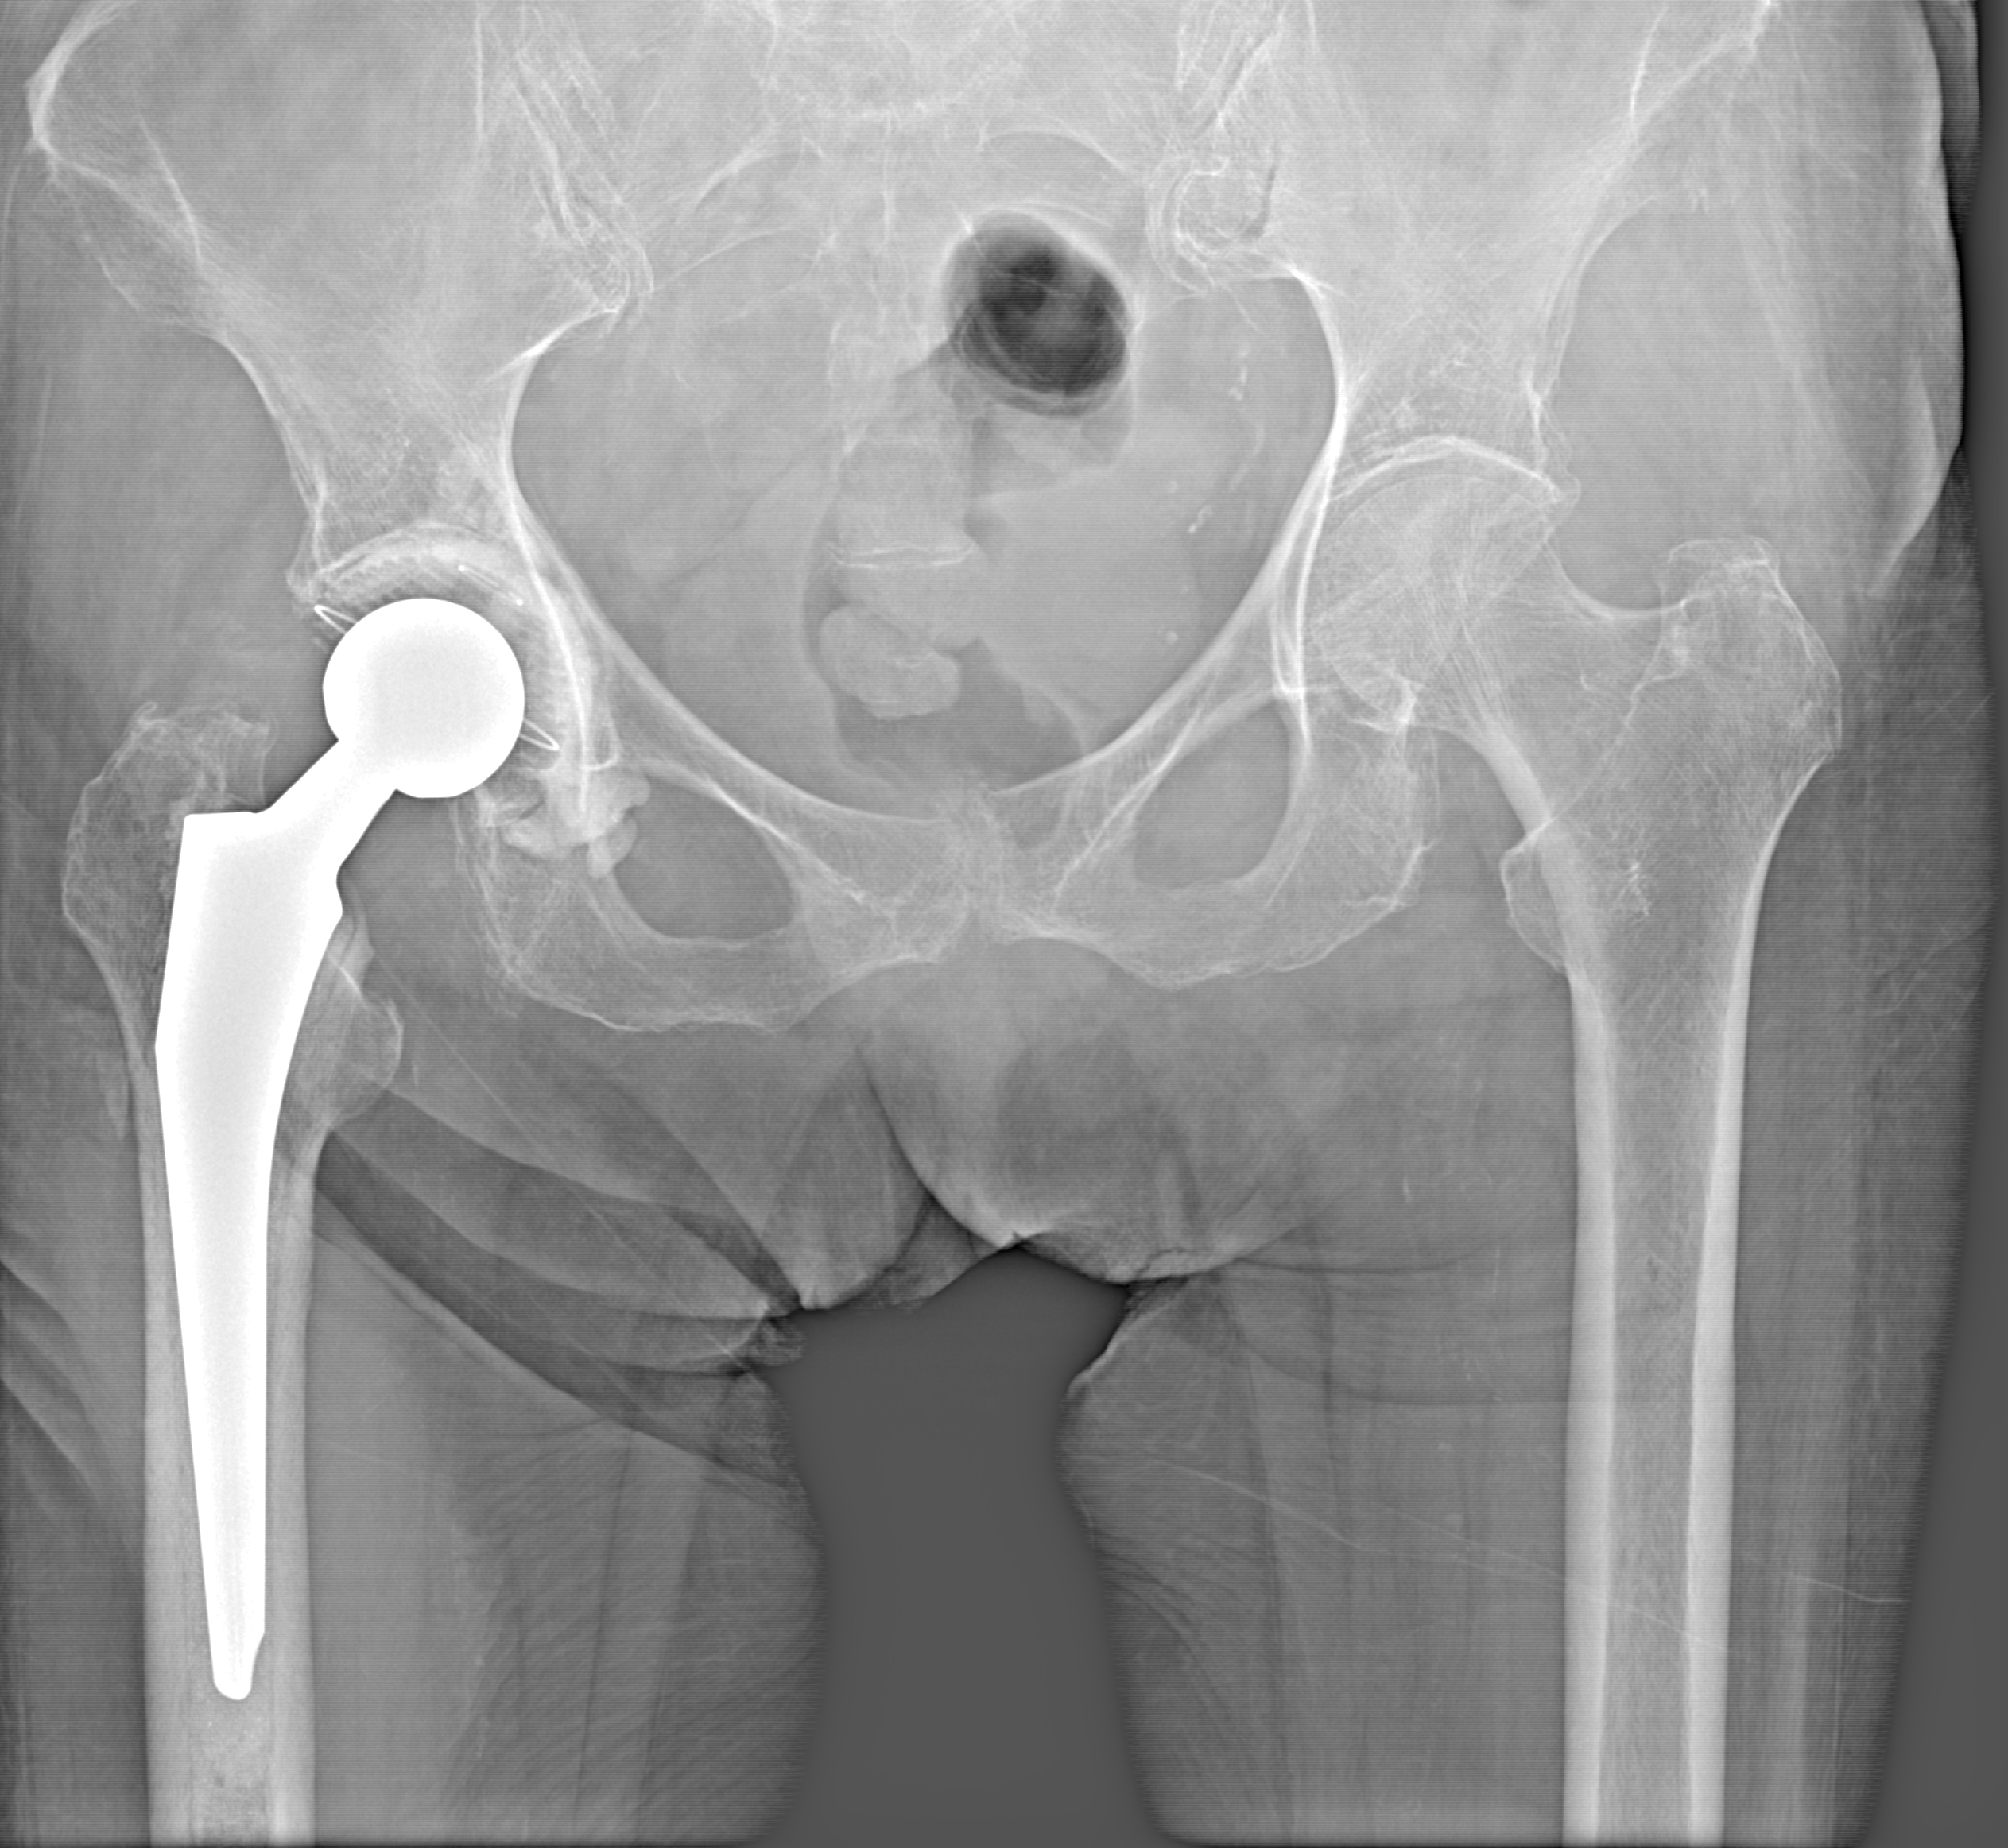

Эндопротез

Рентгенограммы

Рентген на дому: по вашему адресу приезжает врач-рентгенолог, травматолог-ортопед с мобильным рентгеновским аппаратом, проводит диагностику травмы или заболевания, делает необходимые рентгенограммы, дает рекомендации по дальнейшему лечению. Получить качественные снимки в домашних условиях возможно благодаря уникальной методике, разработанной МосРентген Центром для института  Склифосовского